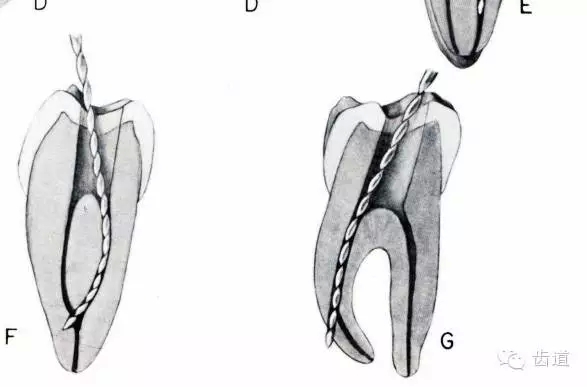

原因:根管銼無(wú)預(yù)彎,換銼過(guò)快,跳號(hào)。

預(yù)防臺(tái)階形成:細(xì)小,彎曲,鈣化根管的預(yù)備時(shí),準(zhǔn)確工作長(zhǎng)度,髓腔內(nèi)充滿NaClO預(yù)彎06#,08#10#根管銼,逐漸達(dá)到工作長(zhǎng)度,采用逐步根管銼預(yù)備法,1-3mm短程提拉。

早發(fā)現(xiàn)臺(tái)階可去除,25#或30#銼產(chǎn)生的臺(tái)階去除較困難。方法同通過(guò)根管堵塞物。

熟悉根管解剖形態(tài);X線應(yīng)能清楚顯示根管和根尖區(qū);及時(shí)換銼;預(yù)彎根管銼;小號(hào)銼應(yīng)做充分預(yù)備(08#---20#);達(dá)到工作長(zhǎng)度時(shí)不能做旋轉(zhuǎn)預(yù)備;使用H銼前應(yīng)先使用同號(hào)的K銼預(yù)備;換大一號(hào)銼之前,該銼應(yīng)能在根管內(nèi)自由出入;細(xì)小的彎曲根管應(yīng)盡量使用小號(hào)銼充分預(yù)備,避免堅(jiān)硬的大好銼;向彎曲相反方向預(yù)備。